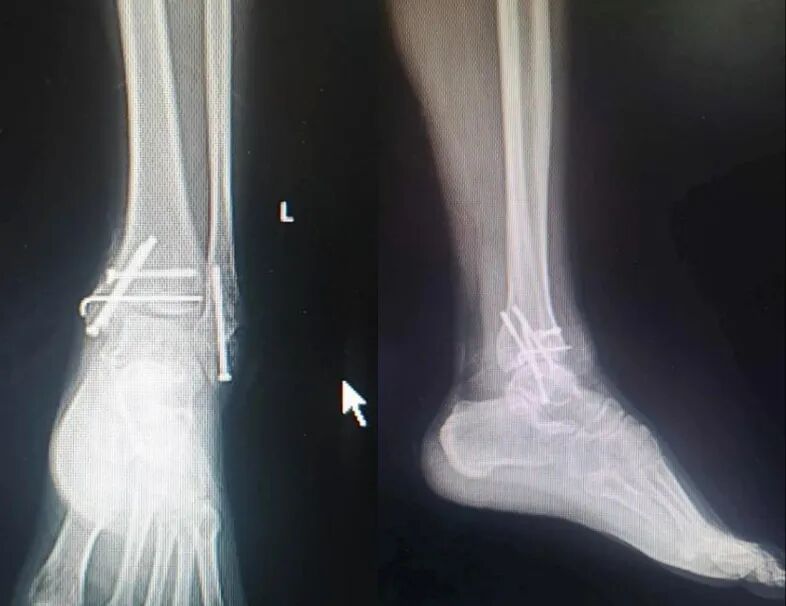

手术后 X 线片

术后 21 个月 X 线片:

患者术后一年半有余,要求去除内固定物来院,未诉不适,大意了,术前阅片不仔细,术中拆除锁钉、螺旋刀片和尾帽,拔主钉后傻眼了 —— 只拔出了上三分之一 ,回头再看片子才发现主钉刚好在螺旋刀片处断裂了。

之前就看骨折愈合得很好,时间也够,当小菜一碟,没有仔细阅片,术中很是被动,想过取,感觉创伤太大,仔细与患者沟通,建议患者不取了,家属也签字了,结果术后还是纠缠不休,最后免费治疗,赔钱走人。教训是惨痛的啊!

还有取出器械与螺钉不配套导致手术时长达 6 小时的;还有螺钉滑丝的;还有患者将片子遗留家中,我要值班医生翻拍电脑上的片子,由于图像模糊导致一个垫片差点遗漏未取出,最后幸亏透视躲过一劫。

上面就是值班医生发给我的片子,大家找找那个差点遗漏的垫片在哪里?